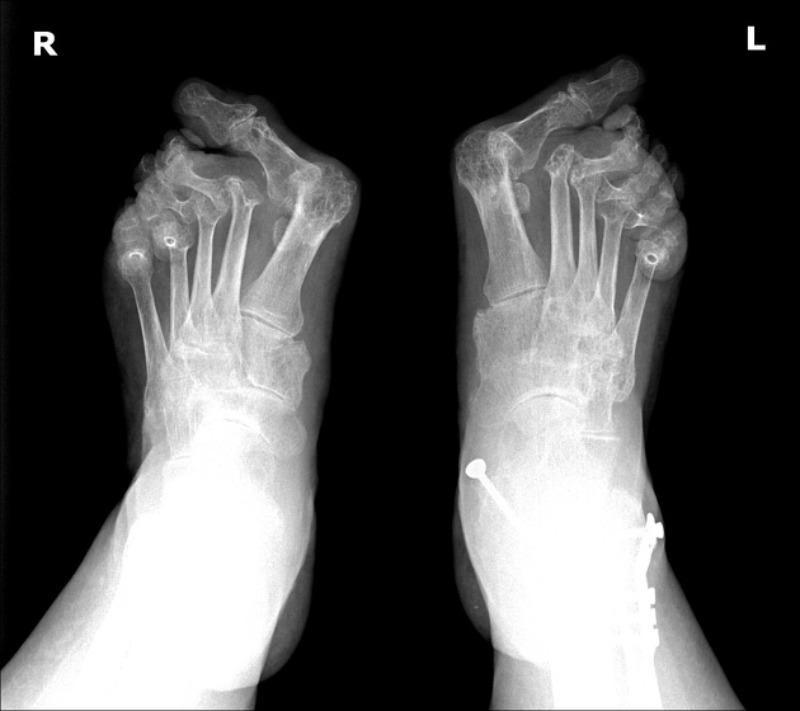

Hình ảnh X-quang ở chân

Hình ảnh X-quang cho thấy tình trạng biến dạng vẹo ngón chân và những bất thường khác, đi kèm với giảm mật độ xương ở bệnh nhân viêm khớp dạng thấp. Ảnh: Radiopaedia

Hình ảnh Xquang ở bàn chân

Ảnh X-quang bàn chân ở một bệnh nhân nữ 55 tuổi bị viêm khớp dạng thấp với tình trạng mòn khớp, biến dạng trật khớp ở khớp đốt bàn – ngón chân. Ảnh: Radiopaedia